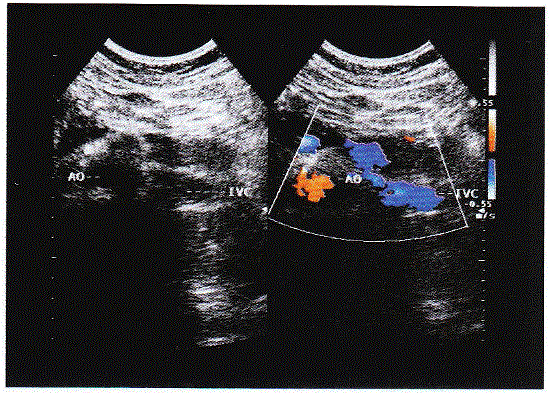

临床资料:女,34岁,右位心。超声综合描述:右上腹可见脾脏(图1),左上腹可见肝脏(图2),腹主动脉位于脊柱右前方,下腔静脉位于脊柱左前方(彩图),胆...

问题 临床资料:女,34岁,右位心。 超声综合描述:右上腹可见脾脏(图1),左上腹可见肝脏(图2),腹主动脉位于脊柱右前方,下腔静脉位于脊柱左前方(彩图),胆囊位于左上腹(图3),各脏器形态大小回声未见异常。 {图1} {图2} {图3} 超声提示:

选项 A.腹腔脏器位置左右反转 B.腹腔脏器位置镜面逆转 C.腹主动脉下腔静脉左右反转 D.腹腔脏器位置正常声像图

答案 A